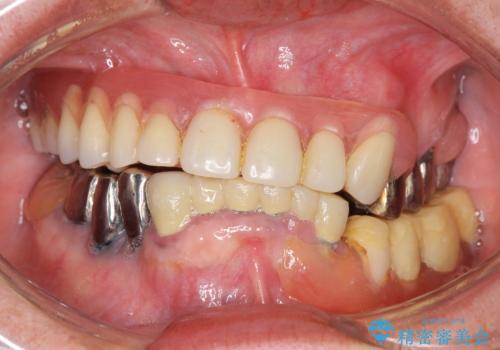

- 他院にて入れ歯を入れたが全体的に左に傾いており、咬みにくく、見た目も気になるといらっしゃった方の症例です。

診査の結果、虫歯が進行し保存できない歯が多かったため抜歯し、磁性アタッチメントを用いたインプラントオーバーデンチャーによる咬合及び見た目の改善を行いました。